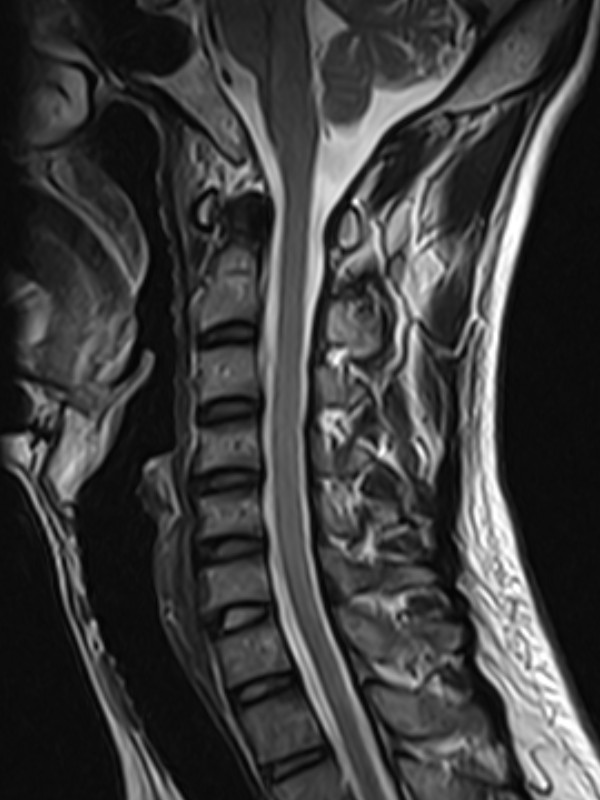

颈椎-T2